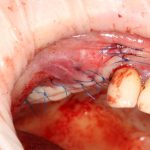

Во-первых, мы получаем возможность прямо подогнать апертуру под анатомические особенности верхнечелюстной полости, во-вторых, получившимся костным фрагментом можно будет легко закрыть доступ даже большого размера:

Кстати, о закрытии окна. Если при создании доступа вы сделаете пропилы немного под углом, то костный фрагмент никогда не провалится через апертуру в верхнечелюстную полость, и у вас не будет проблем с его фиксацией.